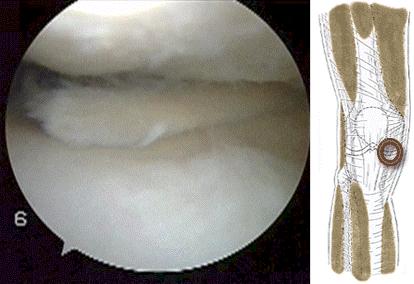

半月板撕裂,尤其是瓣状裂

半月板撕裂以后,尤其是半月板发生了瓣状撕裂就比较容易诱发打软腿。瓣状撕裂有一个特点,患者平时可能会有轻度的疼痛,但是不是特别的严重。

但是在膝关节活动的时候,偶尔会发生半月板撕裂部位的反折,造成瞬间的卡压,患者会表现出明显的打软腿以及比较明显的疼痛,之后需要休息一段时间,缓慢的屈伸膝关节慢慢的才会恢复正常。这种情况说明卡住的撕裂部位,又恢复了常态。(大家看下面这个动图,如果这个破裂的瓣比较大,那么就有可能发生反折和卡别)

还有一种半月板的问题有可能会诱发患者出现打软腿或者是关节的卡片,那就是盘状软骨。这种情况是先天性的变异,正常应该是月牙状的半月板,发育成了满月,形态上看起来像一个盘子,这种情况就容易发生撕裂,诱发患者出现打软腿和疼痛。(下图即为盘状半月板的影像学资料)

诊断半月板的撕裂一样也是需要进行膝关节的核磁检查,明确半月板是否存在撕裂,如果撕裂比较严重,需要进行关节镜手术治疗。